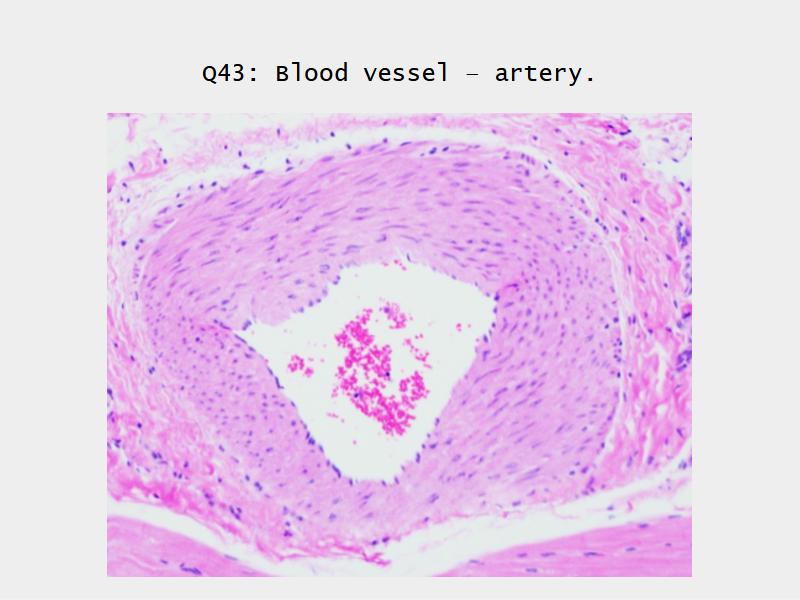

The cardiovascular system needs to be connected to the respiratory system.Path of O2 and CO2

- List complete

- With layers

- And cells

- And function of each